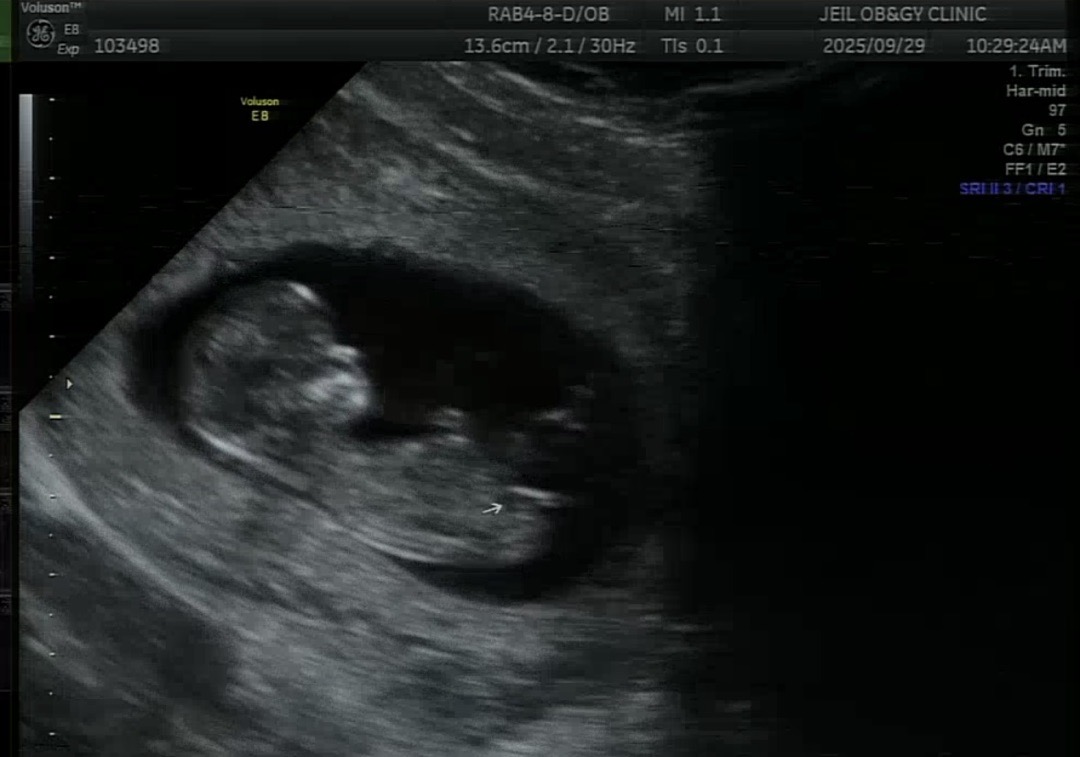

11주3일차 각도법 봐주세요

딸을 원해는데.. 태몽을 아들태몽을 꿔서 아들일지 딸일지 너무 궁금하네요 각도법고수님들!! 알려주세요